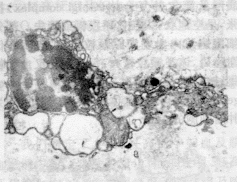

2.1 肿瘤细胞的形态 见照片1。由照片1可见,核质比增大,常染色质明显存在,异染色质呈细颗粒状,散在或边集于核膜下,核仁呈网团状,表明核增殖功能旺盛,细胞质内散在各种细胞器。

肿瘤细胞中,常散在一些形态结构趋向死亡的肿瘤细胞,即凋亡细胞。后者与肿瘤细胞明显不同,而且核的变化似乎发生在其它变化之先。卵巢肿瘤细胞凋亡的规律大致是:先出现核内异染色质增多和边集,常染色质减少,胞浆电子密度增高,细胞体积缩小,相邻细胞间的细胞连接消失,细胞突起减少,见照片2。代表性的变化为异染色质边集呈新月状,见照片3。此时细胞器改变不明显,内质网及线粒体结构完整正常,只是部分细胞溶酶体增多,除初级溶酶体外,更引人注目的是大型次级溶酶体,后者外披单层膜,内含质地不均、高电子密度及空泡状物质。进一步的变化是固缩核呈不均一的块状结构,见照片4。核周间隙增大,且腔隙大小不一,核孔增大,内质网及高尔基复合体(Golgi complex)扩张,呈空泡状,线粒体嵴模糊或消失。部分细胞胞浆内出现糖原颗粒堆积,表明糖代谢障碍,该类颗粒较大,每一颗粒又由细粒集结成簇,故证明属α型糖原颗粒(glycogen granules)。细胞体积进一步缩小,约为肿瘤细胞的1/5~1/4。

照片1 卵巢恶性肿瘤细胞,核质比增大,核异形性明显(×4000)

照片2 细胞凋亡最初的表现,异染色质边集,细胞周围连接消失(×8000)

照片3 典型的异染色质边集呈新月状(×8000)

照片4 核固缩呈块状,胞浆内充满呈空泡状的膨大内质网(×10 000)

照片5 核固缩呈不均匀的点状结构,细胞凋亡小体形成(×8000)

照片6 异吞噬现象,上方为肿瘤细胞的核,下方为降解的细胞凋亡(×6000)